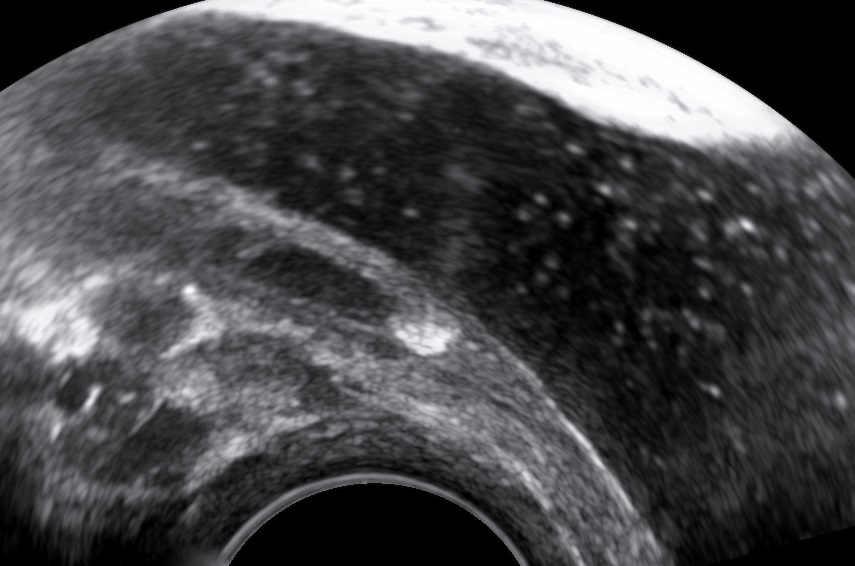

The levator ani muscle avulsion may be demonstrated with 2D Ultrasound, however 3D (or even 4D) Ultrasound as well as MRI are superior in demonstrating avulsion (Dietz 2019).